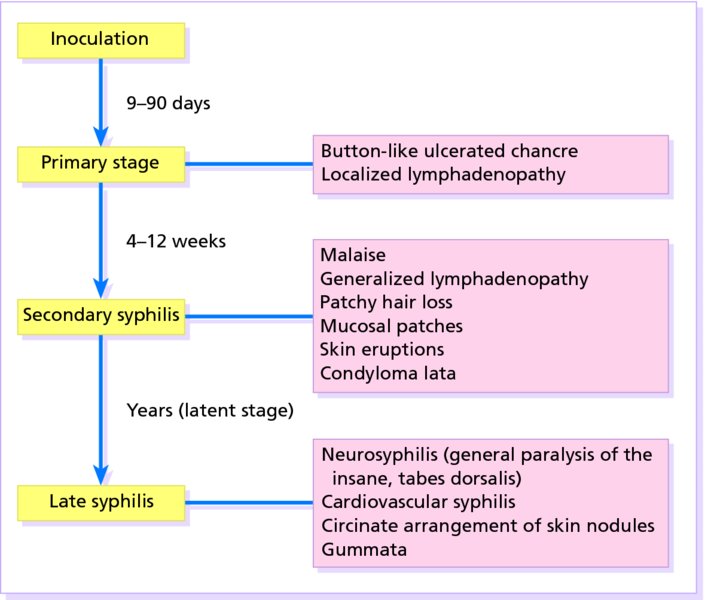

Signs, Symptoms, and Complications of Syphilis

Stages of Syphilis: Symptoms, Causes, Prevention, and Treatment

Syphilis symptoms, stages, and serologic titers timeline. | Download …

Syphilis

Signs and Symptoms – syphilis-the great imitator

Syphilis symptoms, stages, and serologic titers timeline. | Download …